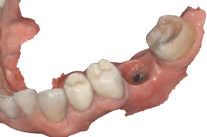

Coroa sobre Implante aparafusada em Modelo impresso. zirconia/cerâmica

Coroa instalada em boca

O fluxo digital na prótese sobre implante proporciona um avanço significativo em termos de precisão, estética e eficiência. Desde o escaneamento até a confecção final, cada etapa é otimizada para garantir resultados de alta qualidade e satisfação do paciente. Laboratórios qualificados e a integração de tecnologias de ponta são essenciais para alcançar resultados satisfatórios.